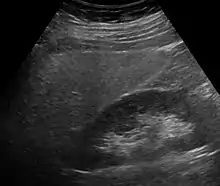

Imaging studies are often obtained during the evaluation process. Ultrasonography reveals a "bright" liver with increased echogenicity. Medical imaging can aid in diagnosis of fatty liver; fatty livers have lower density than spleens on computed tomography (CT), and fat appears bright in T1-weighted magnetic resonance images (MRIs). Magnetic resonance elastography, a variant of magnetic resonance imaging, is investigated as a non-invasive method to diagnose fibrosis progression.[27] Histological diagnosis by liver biopsy is the most accurate measure of fibrosis and liver fat progression as of 2018.[6]